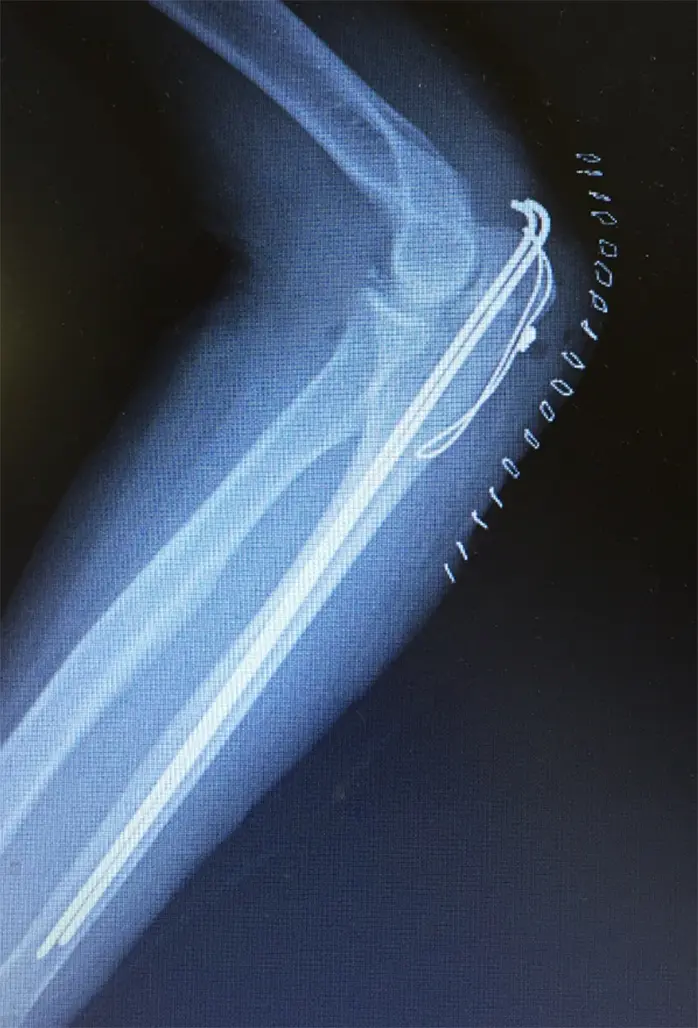

手術記録

骨折部直上で皮切。骨折部展開し、整復阻害となっている血種を除去。平ノミを遠位骨片の骨折部に入れ、関節面を挙上。人口骨オスフェリオンを楔状にして打ち込んで整復とした。単鋭鉤で両骨片間を整復しつつ2.0mm K-wire2本挿入。その後fiber wireと0.97mm軟鋼線でTBW固定とした。固定制良好であることを確認し、洗浄、閉創、終了とした。

本症例は肘頭骨折、Muller AO分類21-C1と診断される。関節内骨折では肘頭骨折の治療で重要なのは、重力を排除した状態で肘関節の自動進展運動ができるか否かである。今回は鈎状突起より近医の単純骨折であり8の字型テンションバンド法で固定することとなった。テンションバンドとは対側皮質骨にかかった張力を圧迫力に変換することである。ワイヤーループによるテンションバンドの原理は、膝蓋骨と肘頭の関節内骨折に広く用いられ、骨折の関節側で筋力由来の張力を圧迫力に変換している。加えて小さな裂離骨折もテンションバンド固定原理が有効である。本症例のような肘頭骨折の場合では、テンションバンドのループは尺骨近位に開けた2mmのドリル孔を通し、上腕骨近位部ではスクリューヘッドがアンカーの役割を果たしている。注意点としてはインプラントの折損である。純粋に張力のみが作用した場合はワイヤーは十分な強度があるが、屈曲応力が加わると金属疲労によりすぐ破損するからである。